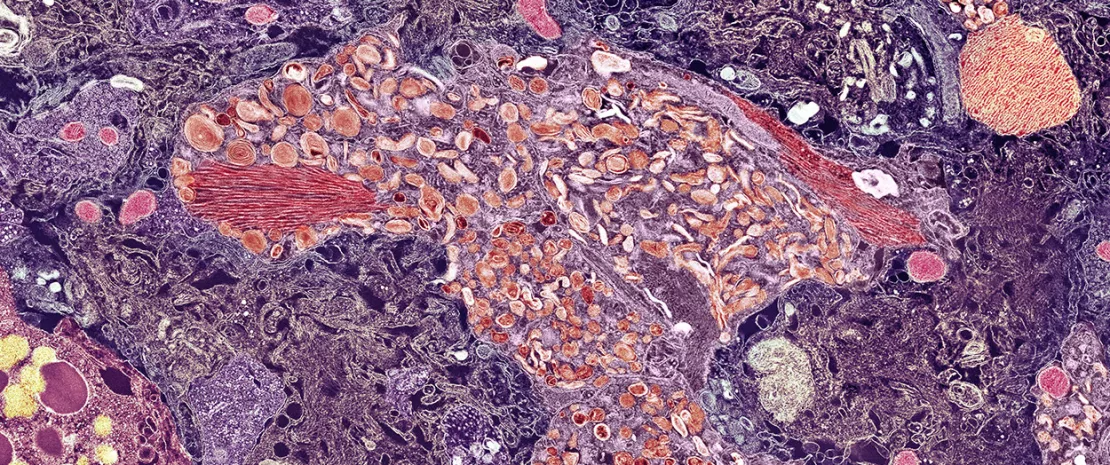

Durante anos, a comunidade científica vem reunindo evidências de que o nosso intestino e o cérebro estão em constante comunicação, um conceito conhecido como eixo intestino-cérebro1, 2. Vimos que a composição da microbiota intestinal é diferente em pacientes com doença de Alzheimer3, e que esta disbiose pode contribuir para a neuroinflamação que alimenta a doença4, 5.

Utilizando o (sidenote: Sequenciamento metagenómico Método de sequenciamento de alta resolução que analisa todo o material genético de cada micróbio numa amostra. Ao contrário de técnicas mais antigas que apenas identificam famílias bacterianas, este método permite uma identificação precisa do nível da espécie e revela os genes funcionais que essas bactérias possuem. ) de alta resolução em pacientes com (sidenote: Défice Cognitivo Ligeiro (DCL) O DCL é um estágio clínico entre o declínio cognitivo esperado do envelhecimento normal e o declínio mais grave da demência. Os indivíduos com DCL têm problemas percetíveis de memória ou pensamento, mas ainda podem realizar a maioria das atividades diárias, o que representa uma janela crítica para intervenção e estudo. ) , um estágio intermediário crítico, os investigadores descobriram que não havia diferença significativa na diversidade geral da microbiota intestinal em comparação com controlos saudáveis. Em vez disso, constataram que a diferença crucial residia na identidade dos atores. O estudo identificou 59 espécies microbianas específicas cuja presença ou ausência estava diretamente correlacionada ao DCL, às placas amiloides e aos níveis de (sidenote: Proteína Tau A Tau é uma proteína que normalmente estabiliza o sistema de transporte interno, ou microtúbulos, no interior das células nervosas do cérebro. Na doença de Alzheimer, torna-se anormalmente fosforilada e agrega-se em emaranhados neurofibrilares dentro dos neurónios, levando à disfunção celular e à morte. ) , as principais características patológicas da doença de Alzheimer. Isto revela que não se trata do tamanho do exército microbiano, mas de quais soldados específicos estão na linha de frente.

O estudo vai além da mera correlação, identificando bactérias que não estão apenas presentes, mas são funcionalmente ligadas à saúde do cérebro. Uma das espécies benéficas identificadas, a Akkermansia muciniphila, foi negativamente correlacionada com a carga amiloide. Este dado é significativo, pois a Akkermansia é conhecida por produzir metabólitos que fortalecem a barreira intestinal e têm efeitos anti-inflamatórios7. Esta investigação sugere que o seu papel pode ser ainda mais direto, e que potencialmente influencia o metabolismo energético do cérebro e o protege contra o acúmulo de proteínas tóxicas, como a proteína Tau.